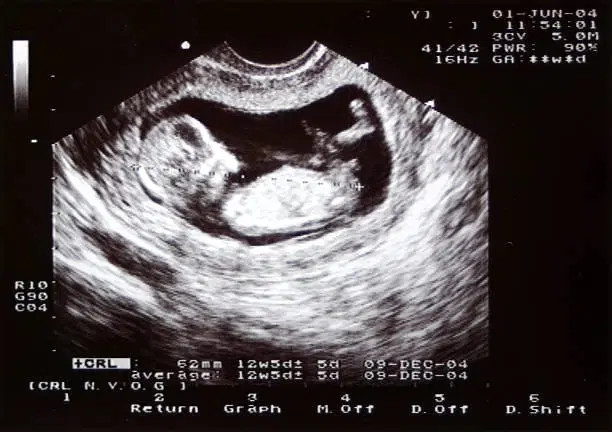

2 Boyutlu (2D) Ultrason Nedir?

2D ultrason, gebelik takibinin temel taşıdır.

👉 Tıbbi tanının ana yükünü 2D ultrason taşır.